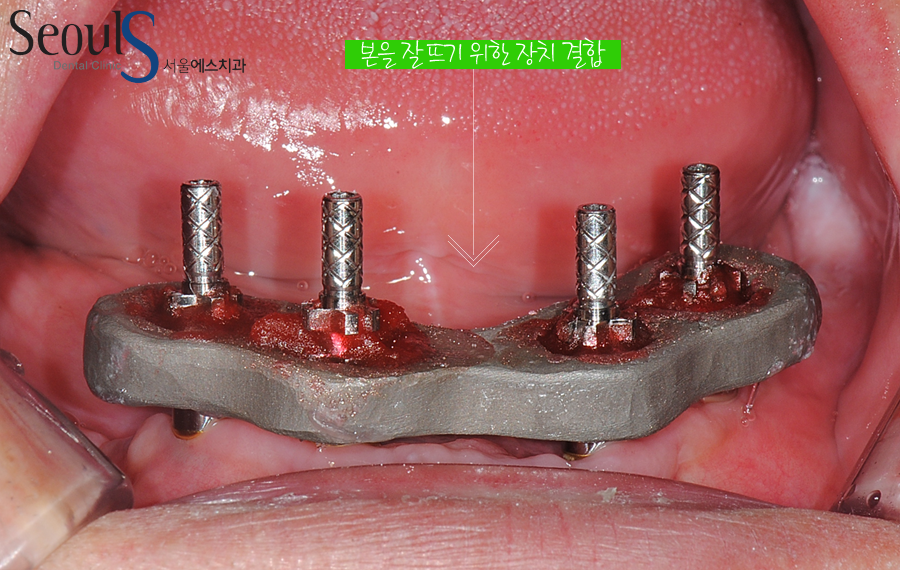

아랫니, 임플란트와 잇몸뼈가 단단히 굳어 치아를 제작하기 위해 본을 뜨고 있는 모습입니다

본을 뜨기 위해서 장치를 결합한 모습으로 앞에서도 이야기했는데

임플란트를 정확한 위치에 식립하는 것도 중요하지만

최대한 자연스럽고 이쁜 치아를 제작 및 결합하기 위해

저희 광진구 서울에스치과에서는 임플란트 본을 뜰 때 번거로움이 있을 수 있지만

이쁘고 정확한 보철물을 위해 꼭~~ 장치를 이용해 정확히 본을 뜨고 있습니다

장치를 이용해서 본을 뜨고

아랫니 치아를 제작해 결합했습니다